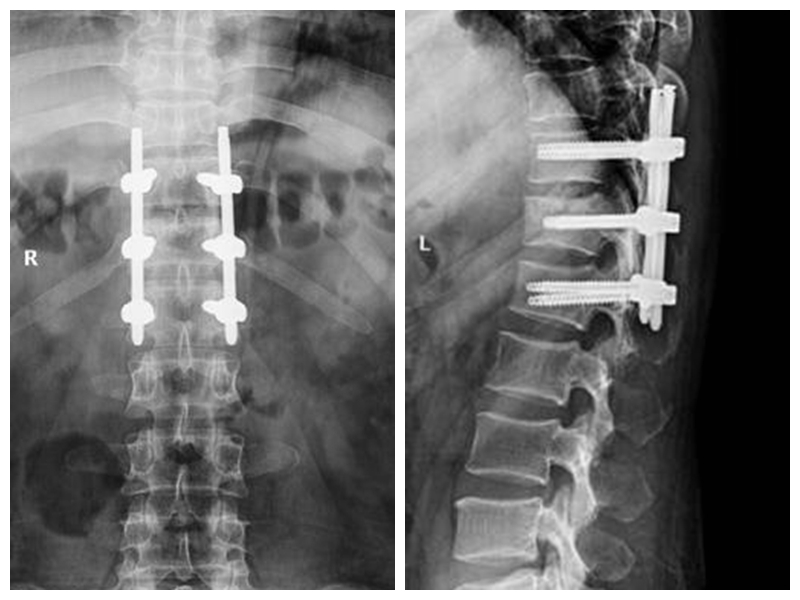

經(jīng)皮胸腰椎骨折椎弓根螺釘內(nèi)固定技術(shù)

傳統(tǒng)胸腰椎骨折切開復(fù)位椎弓根螺釘內(nèi)固定術(shù)組織創(chuàng)傷大、失血量大、住院時(shí)間長、下地時(shí)間晚、費(fèi)用高。經(jīng)皮胸腰椎骨折椎弓根螺釘內(nèi)固定技術(shù)組織創(chuàng)傷小、失血少、住院時(shí)間段、下地時(shí)間早、費(fèi)用低。

典型病例:患者**,男性,43歲,因“摔傷致胸腰背部疼痛、活動(dòng)受限2小時(shí)”門診平車入院。雙下肢肌力、感覺及肌張力正常。

本例患者術(shù)后5天在腰圍保護(hù)下獨(dú)立下床,雙下肢肌力感覺正常。